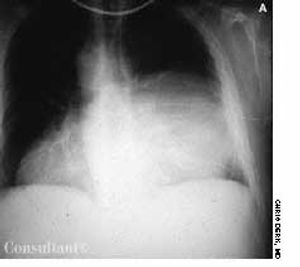

A 44-year-old black man presented to our office with insidious onset of blurred vision. He had no significant past medical history but complained of dyspnea on exertion. On examination, the left pupil was irregular and fixed. A chest film demonstrated bilateral hilar adenopathy. Laboratory findings included normal purified protein derivative test results and elevated angiotensin-converting enzyme levels; pulmonary function studies appeared normal.